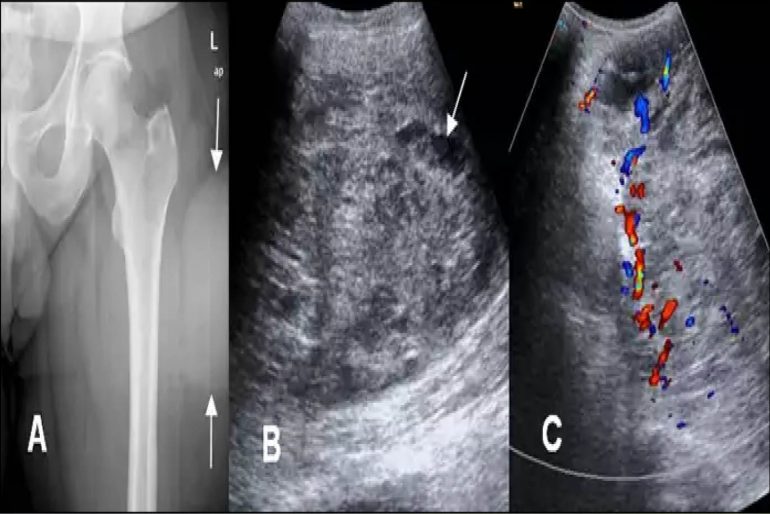

Case example of a patient with a retroperitoneal A frail